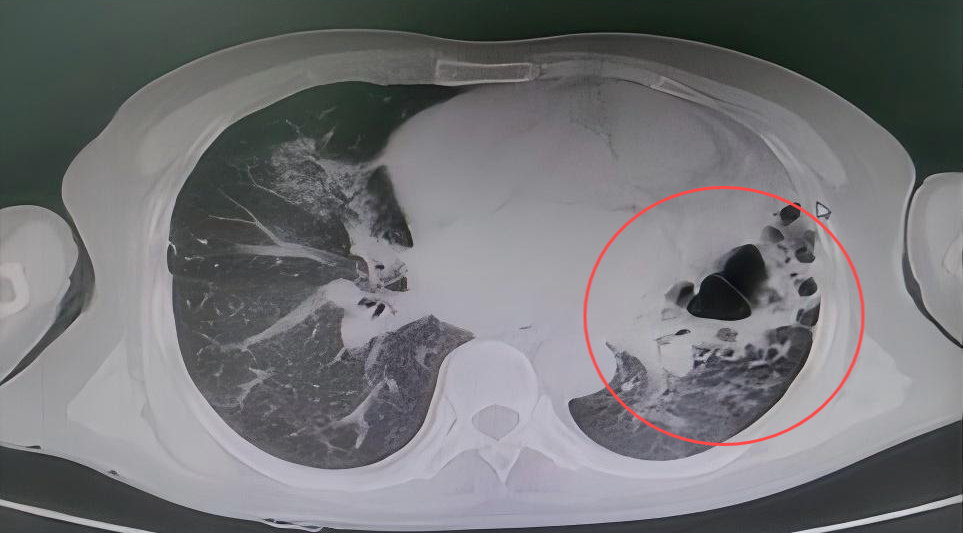

在实施支气管动脉栓塞术止血后,考虑到患者大量咯血后血液会阻塞气道,科室团队当即进行CT扫描,发现右肺已被凝血块完全阻塞,立即在床边通过气管镜清理气道内凝血块。术后,患者再无咯血,经住院治疗一段时间后,患者复查CT右肺基本恢复,顺利出院。

大量咳血后CT显示右肺完全阻塞

床边支气管镜清理凝血块